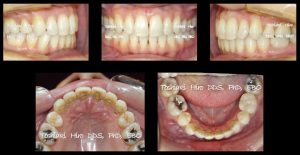

トップバッターは私、矯正歯科の意義と目的にはじまり、舌側矯正症例10数症例を紹介しました。